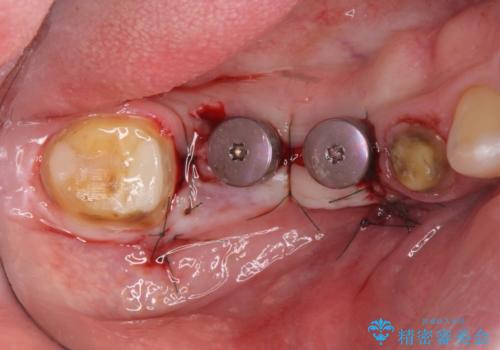

長いブリッジをインプラント補綴への変更

支台を増やし、残った歯の負担を減らし守るために欠損部位にインプラントを埋入し咬合力の負担に対応できる環境を整えます。

- 105.4万円(仮歯×4・ストローマンインプラント×2・チタンカスタムアバットメント×2・ジルコニアクラウン×4)費用は治療当時の料金となります

インプラント治療は、ブリッジや入れ歯と異なり人口の歯根となるインプラントを顎骨内に埋入することで咬合力に耐える支台を増やせるというメリットがあります。

残った歯の負担を減らすことでより長期的な予後を期待することができます。